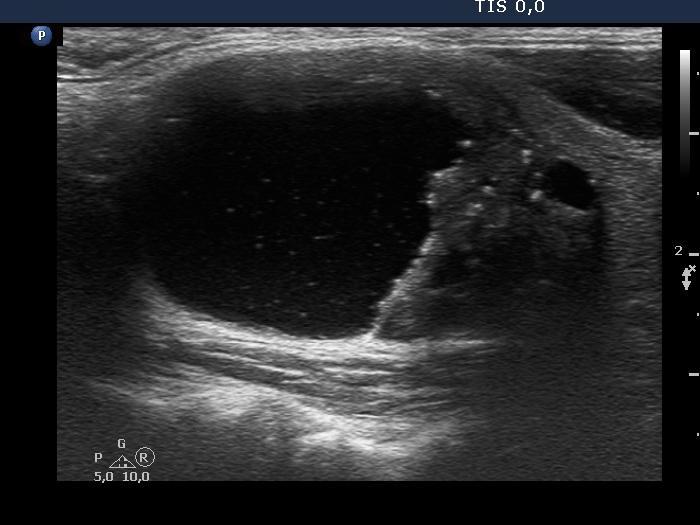

The composition of the nodule - case 126

Second session of sclerotherapy (ultrasonographic picture 4)

Left lobe, another longitudinal scan.